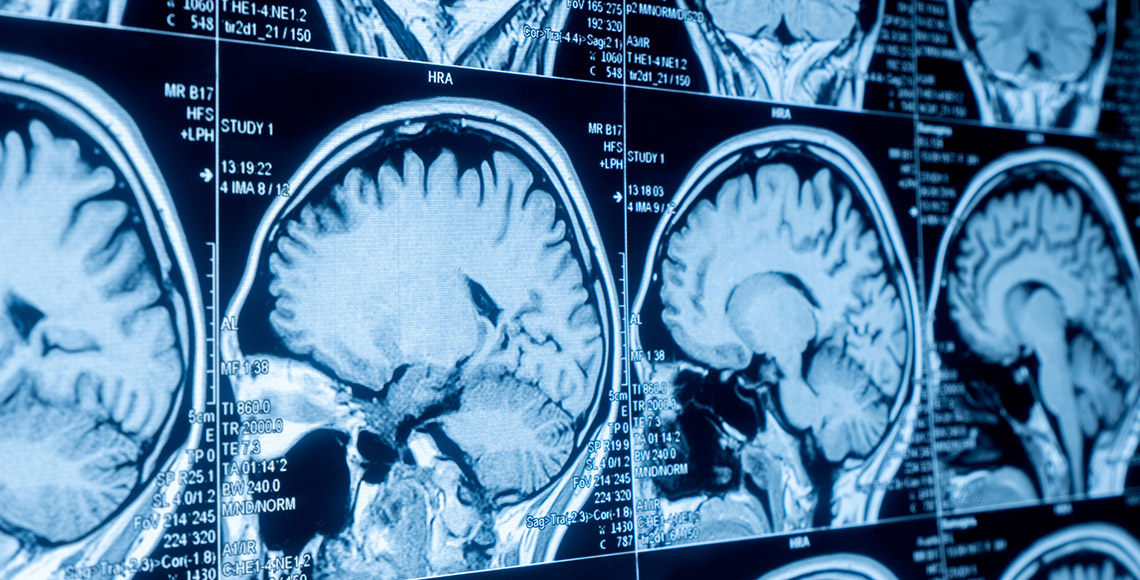

Magnetna rezonanca glave je precizna metoda za dijagnozu moždanih stanja poput tumora i šloga. Pregled je neškodljiv, ali kontraindikovan za pacijente s metalnim implantima.

Magnetna rezonanca glave 1.5T - MRI endokranijuma | 11.950 RSD |

Magnetna rezonanca angiografija glave (magistralnih arterija) 1.5T - MRI angiografija arterija endokranijuma | 11.950 RSD |

Magnetna rezonanca angiografija glave (vena i venskih sinusa) 1.5T - MRI venografija endokranijuma | 11.950 RSD |

Multislajsni CT skener glave - MSCT endokranijuma, mozga | 8.600 RSD |